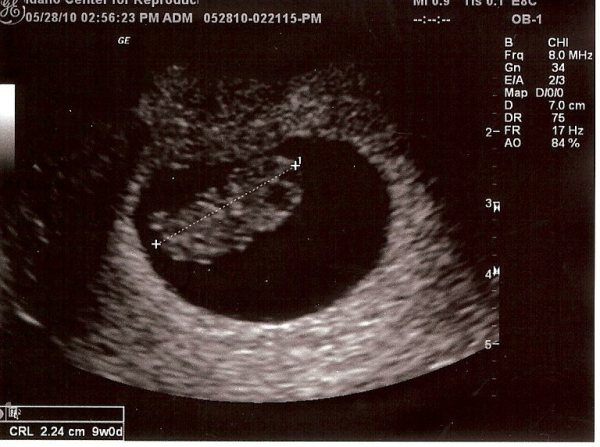

Ultrasound #2 8 Weeks 6 Days May 28th 2010

Our little baby at 8weeks and 6days. Measuring one day advanced at 9weeks 0days. Although I'm still determined to deliver ON my due date! (@ 1:11am!)